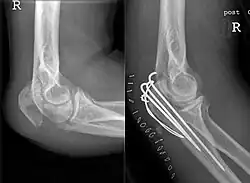

Fracture (left) and repair (right) with three pins, wires, and incision closure with staples

Tension band fixation

Tension band fixation is the most common form of internal fixation used for non-comminuted olecranon fractures.[5] It is typically reserved for noncomminuted fractures that are proximal to the coronoid.[2] This procedure is performed using Kirschner wire (K-wires) which converts tensile forces into compressive force.[2]